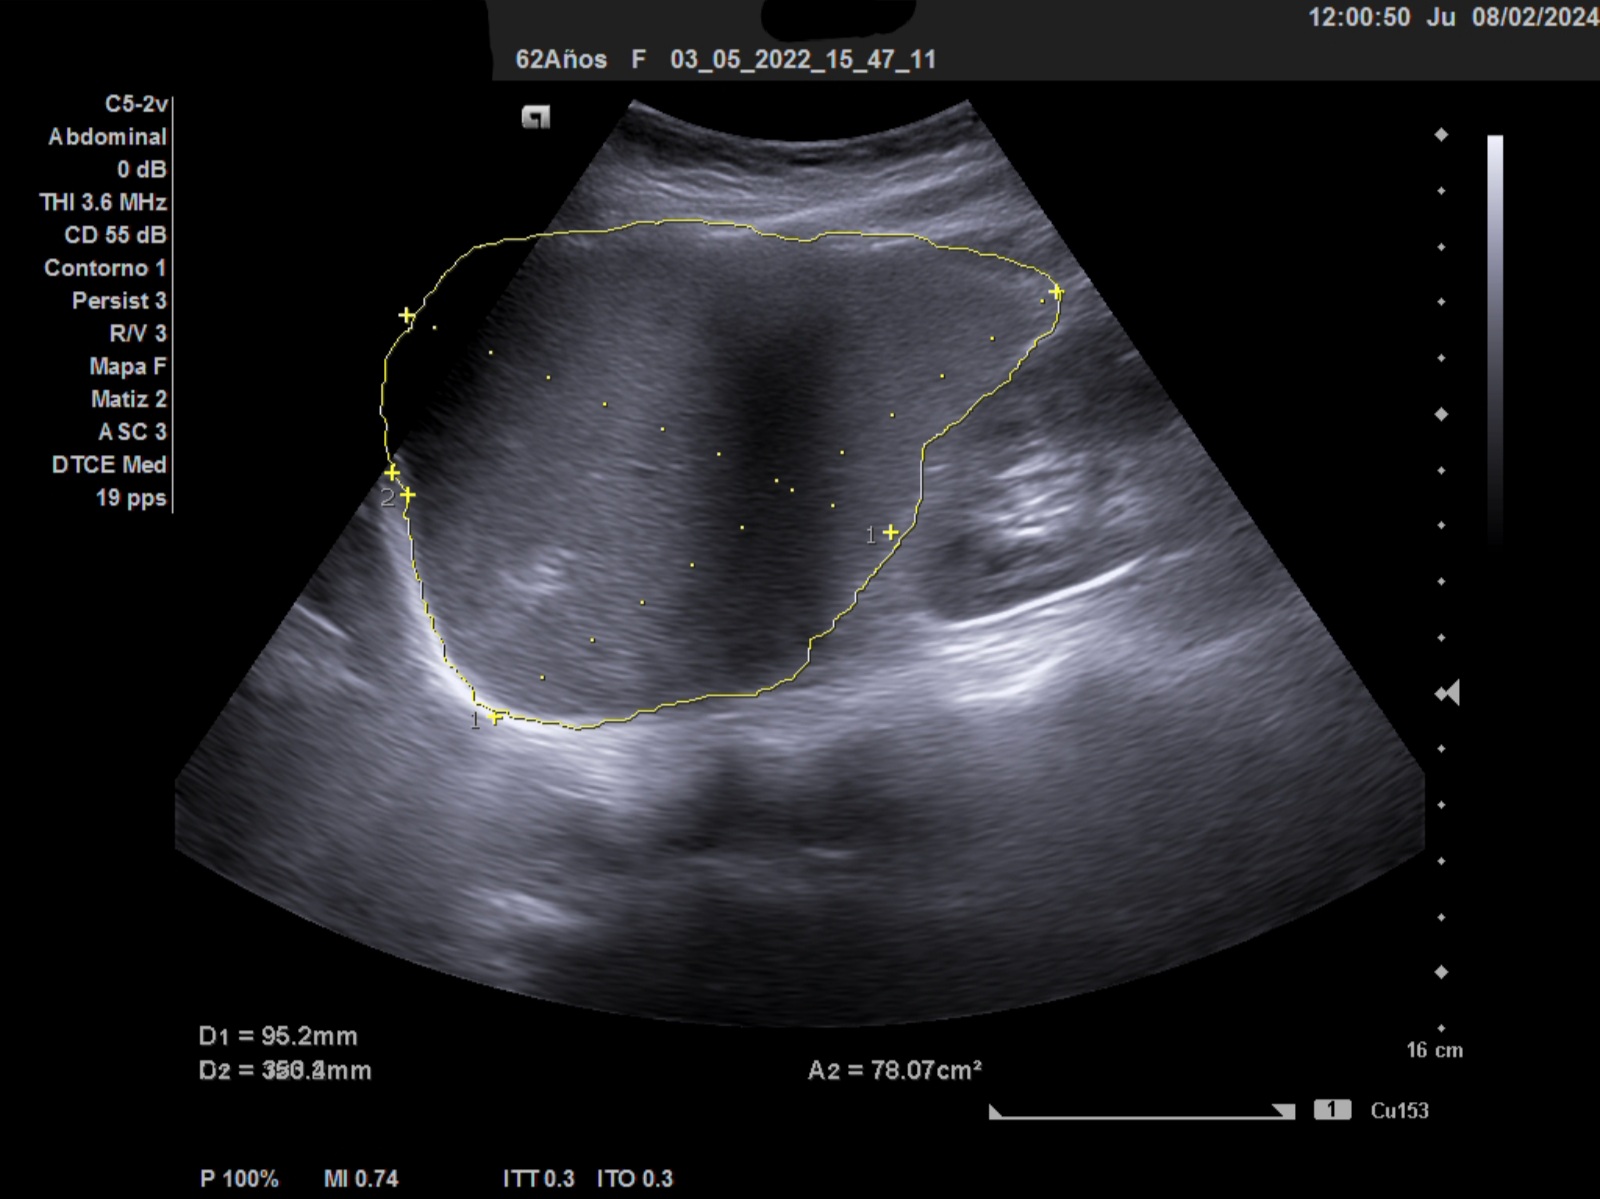

Ecografía clínica: Esplenomegalia con bazo de 12,6 mm eje longitundinal, 9,5 mm transversal y un area 71 cm2 (patológico por encima de 55)

La ecografía clínica debe ser exhaustica, a nivel de hipocondrio izquierdo debe localizarse el bazo con inspección del parénquima, bordes e hilio, debe medirse los 2 diámetros y a eso añadir el area. Se considera patoñogico un diámetro por encima de 12 mm eje longitudinal, >5mm eje transversal y el area por encimad e 55 cm2. En casos de gran esplenomegalia orientará hacia etiología infecciosa: parasitaria, vírica o bacteriana.

Ante la detección de una alteración en el hemograma como la bicitopenia, nos planteamos la ecografía para complementar la ananmesis y la exploración física. La ecografía abdominal debe ser sistemática y exhaustica, inspeccionando las visceras en su totalidad. En el hipocondrio izquierdo puede ser una compleja la visualización completa del bazo. Deben medirse en sus 3 ejes incluyendo el área.